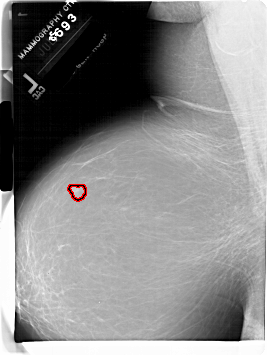

A_1882_1.LEFT_MLO

LEFT_MLO LINES 6736 PIXELS_PER_LINE 5071 BITS_PER_PIXEL 12 RESOLUTION 43.5 OVERLAY

FILE: A_1882_1.LEFT_MLO.OVERLAY

TOTAL_ABNORMALITIES 1

ABNORMALITY 1

LESION_TYPE MASS SHAPE LOBULATED MARGINS CIRCUMSCRIBED

ASSESSMENT 3

SUBTLETY 5

PATHOLOGY BENIGN

TOTAL_OUTLINES 1

BOUNDARY